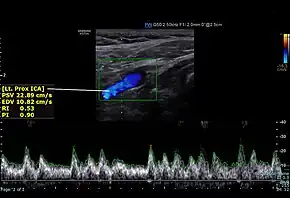

![]() Screenshot of a normal proximal internal carotid artery spectral Doppler | |

Doppler ultrasound allows for assessment of carotid arterial blood flow. Blood flow velocity is increased in areas of stenosis compared to normal. Therefore, doppler imaging substantially aids in the diagnosis of carotid artery stenosis by ultrasound.[2] Internal carotid artery (ICA) is located posterolateral, and larger when compared to the external carotid artery (ECA). ICA has low resistive pattern (difference between the blood velocities during heart systole and diastole) when compared to ECA.[3] ICA has sudden increase in velocity of blood flow during systole and persistent forward blood flow during diastole.[5][6] ICA peak systolic velocity more than 125m/sec and diastolic velocity more than 40 m/sec signifies stenosis.[3]